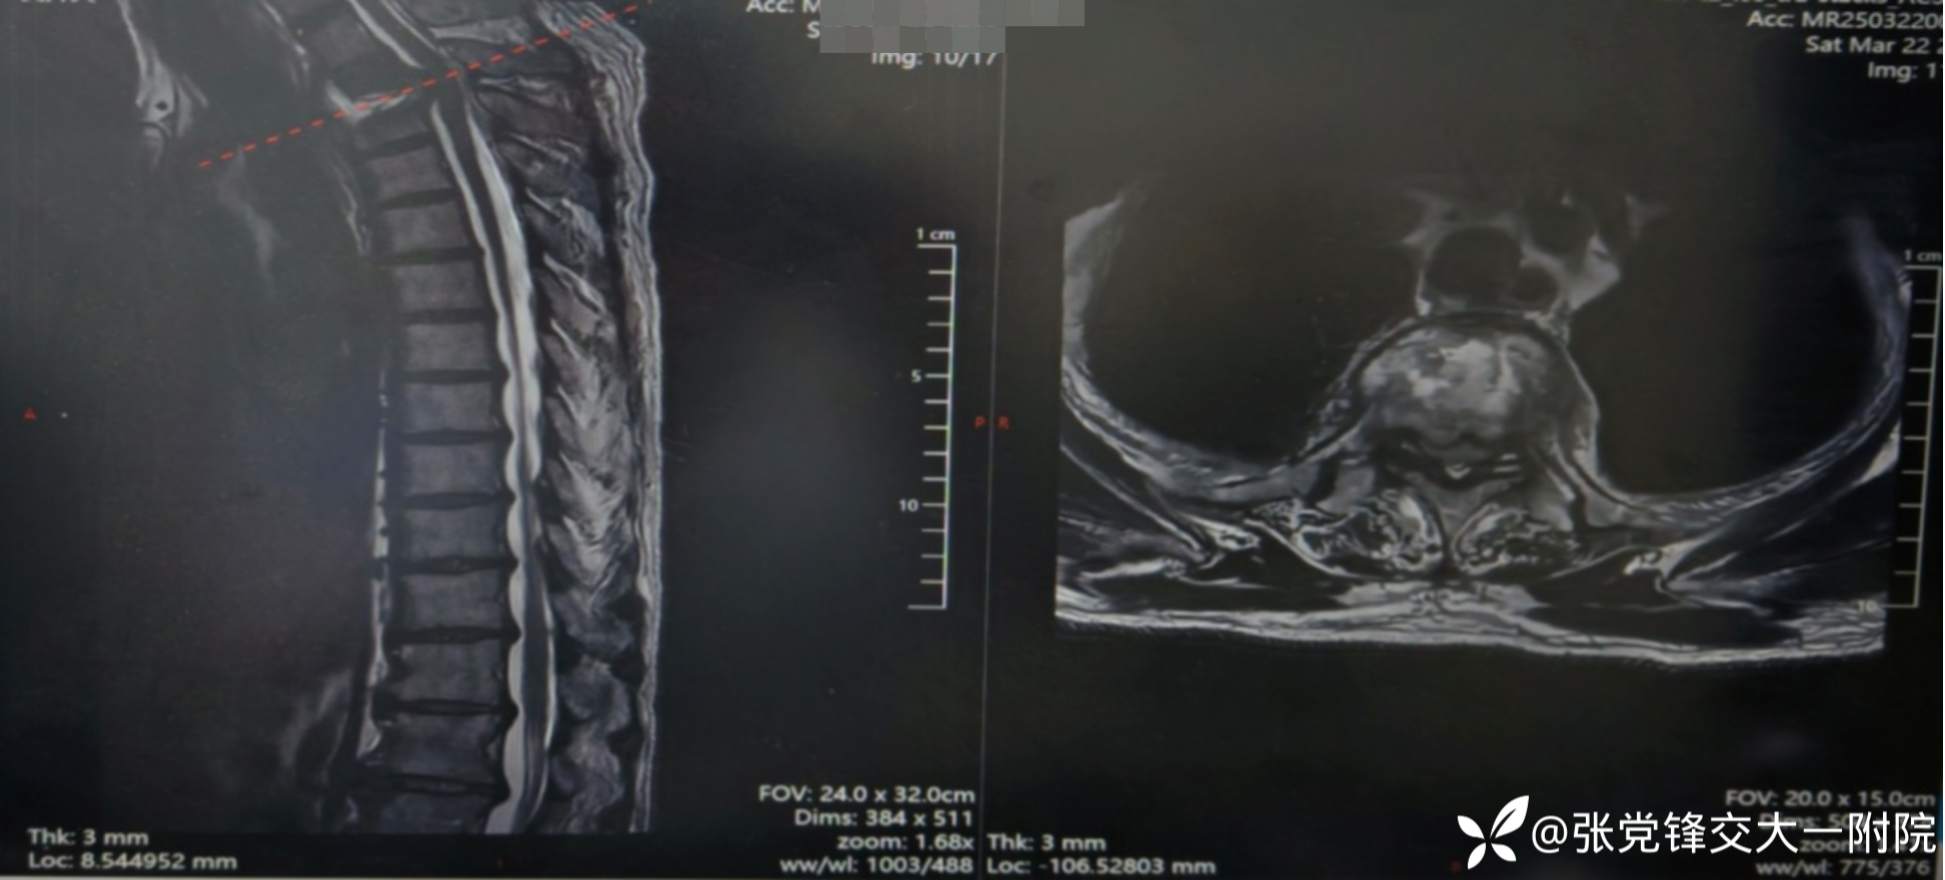

【影像学检查】

术前MRI

术前CT